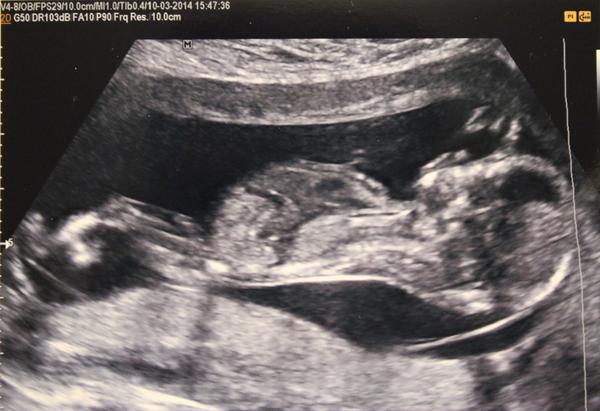

@kremrolka01 Ahoj prosim,poznala by jsi z fotky z Utz zda by to mohla byt holcicka či klucik? Na screeningu nám doktor rekl 80%holcicka...😁 tak jestli jsi to na utz mela jinak.Dekuji moooc.

@ramottka ahoj,mohu otravovat a zeptat se zdá z fotky z Utz poznáš zda holcicka či klucik když poslu?😀 dekuji moooc